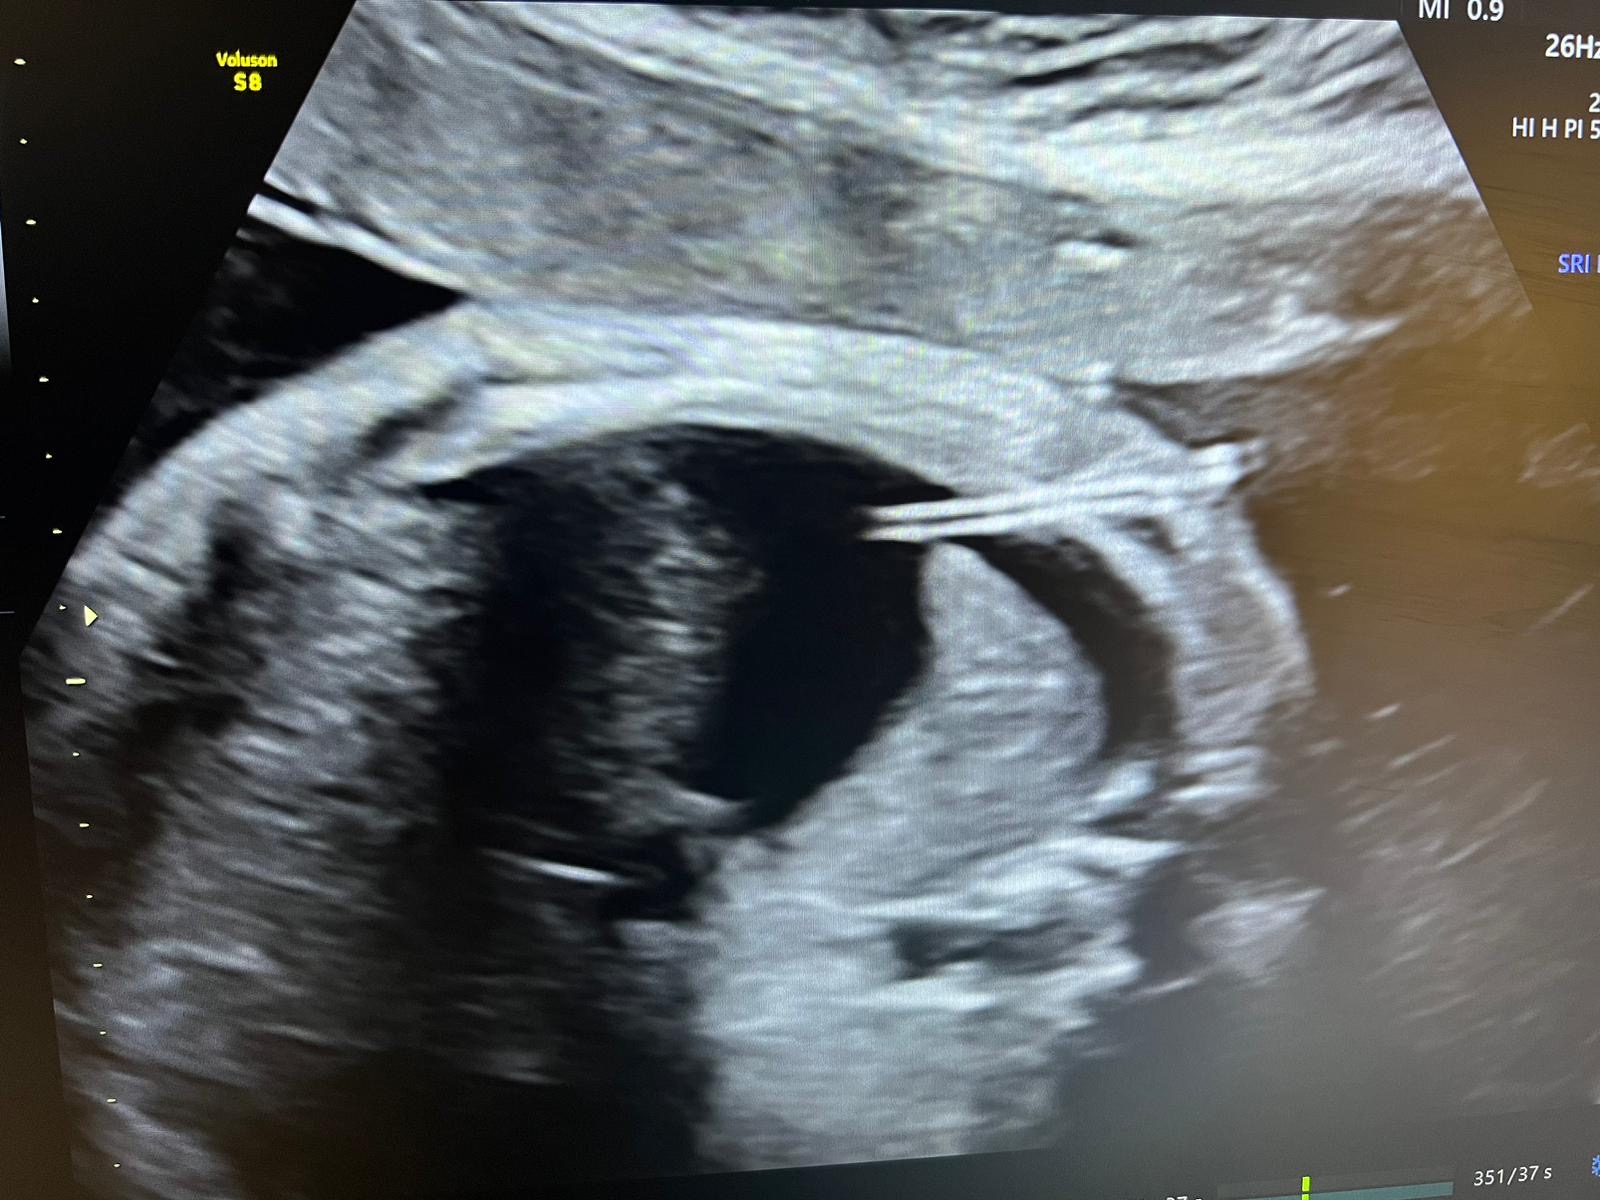

W ostatnich dniach w Klinice Położnictwa i Perinatologii Państwowego Instytutu Medycznego MSWiA w Warszawie wykonano kolejny zabieg z zakresu terapii płodu - po raz pierwszy w tej lokalizacji. U ciężarnej, będącej w 31 tygodniu ciąży, zdiagnozowano hydrothorax u płodu. Jest to nieprawidłowość, polegająca na obecności wolnego płynu w klatce piersiowej płodu, co uniemożliwia prawidłowy rozwój płuc i powoduje ich hypoplazję, jak również przemieszcza i uciska serce, prowadząc do niewydolności krążenia, która - w przypadku braku odpowiedniej terapii - może doprowadzić do śmierci płodu. Przyczyny takiego stanu mogą być natury genetycznej, infekcyjnej, endokrynologicznej, ale najczęściej pozostają nieznane - w takiej sytuacji rozpoznajemy postać idiopatyczną. Terapia hydrothorax polega na odbarczeniu płynu z klatki piersiowej płodu - można to uzyskać poprzez punkcję igłową, jednakże postępowanie takie jest mało efektywne, gdyż szybko dochodzi do nawrotu. Dlatego też metodą z wyboru jest założenie tzw. shuntu opłucnowo-owodniowego (cewnik typu double pig-tail), który umożliwia stały jednokierunkowy drenaż nadmiaru płynu.

Załączone zdjęcia pokazują zabieg (1), który wykonał zespół w składzie dr n. med. Michał Lipa i prof. dr hab. Mirosław Wielgoś oraz obrazy ultrasonograficzne, na których uwidoczniono sytuację wyjściową (2), założony shunt (3) i stan 4 dni po zabiegu (4). Doraźny efekt jest - jak widać na zdjęciach - bardzo dobry, w związku z czym Pacjentkę wypisano do domu. Z niecierpliwością oczekujemy na kontrolę, która odbędzie się w naszej Poradni Patologii Ciąży już za tydzień.